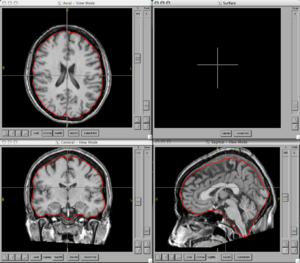

BRAINSCut is a software package for segmentation of structures using artificial neural networks. Currently this tool supports the segmentation of the following structures: brain, caudate, putamen, thalamus, hippocampus, anterior cerebellum, interior posterior cerebellum, superior posterior cerebellum, corpus medullary. Future regions will include the globus pallidus, amygdala, and nucleus accumbens. The command line uses the Slicer3 execution model framework.

Figures

- BRAINSCut